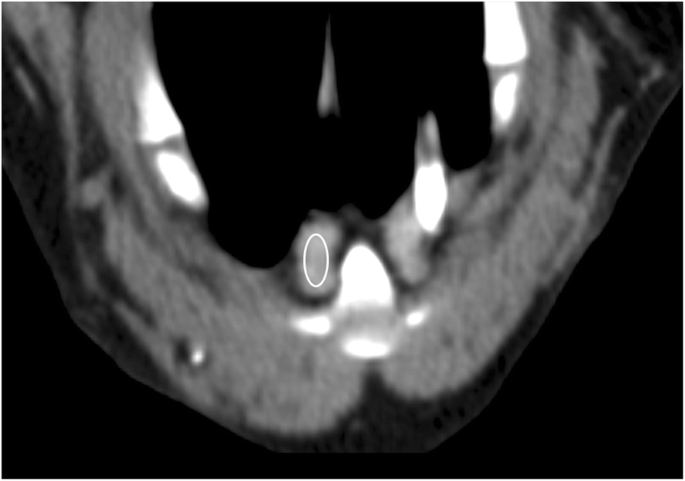

Computed Tomography Measurements Of Presumptively Normal Canine Sternal Lymph Nodes Bmc Veterinary Research Full Text